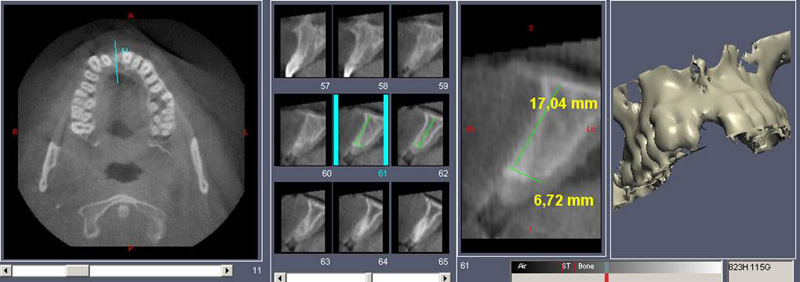

Náhrada jednoho zubu

Klasickým příkladem a indikací pro použití implantátu je ztráta jednoho zubu (v tomto případě v předním – frontálním úseku) v jinak zdravém, nepoškozeném chrupu.

Náhrada jednoho zubu pomocí implantátu je možná také v postranním úseku chrupu. Při ztrátě většího počtu zubů ve frontálním nebo postranním úseku může být mezer uzavřena větším počtem jednotlivých implantátů.